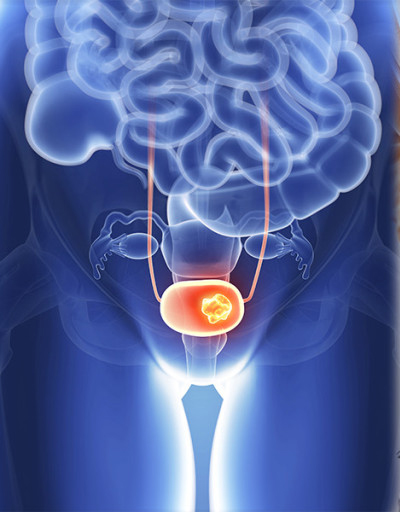

오늘은 남성에게 발생하는 주요 암 중 하나인 전립선암의 초기 증상에 대해 이야기하려 합니다. 전립선암은 초기에는 증상이 매우 미미하거나 전립선 비대증과 같은 양성 질환과 유사하여 간과하기 쉽습니다.

전립선은 방광 바로 아래에 위치하며 요도를 감싸고 있기 때문에, 전립선에 암이 발생하면 주로 소변(배뇨)과 관련된 증상들이 초기부터 나타나는 경우가 많습니다. 다음은 전립선암 환자들이 흔히 겪는 10가지 주요 초기 증상입니다.